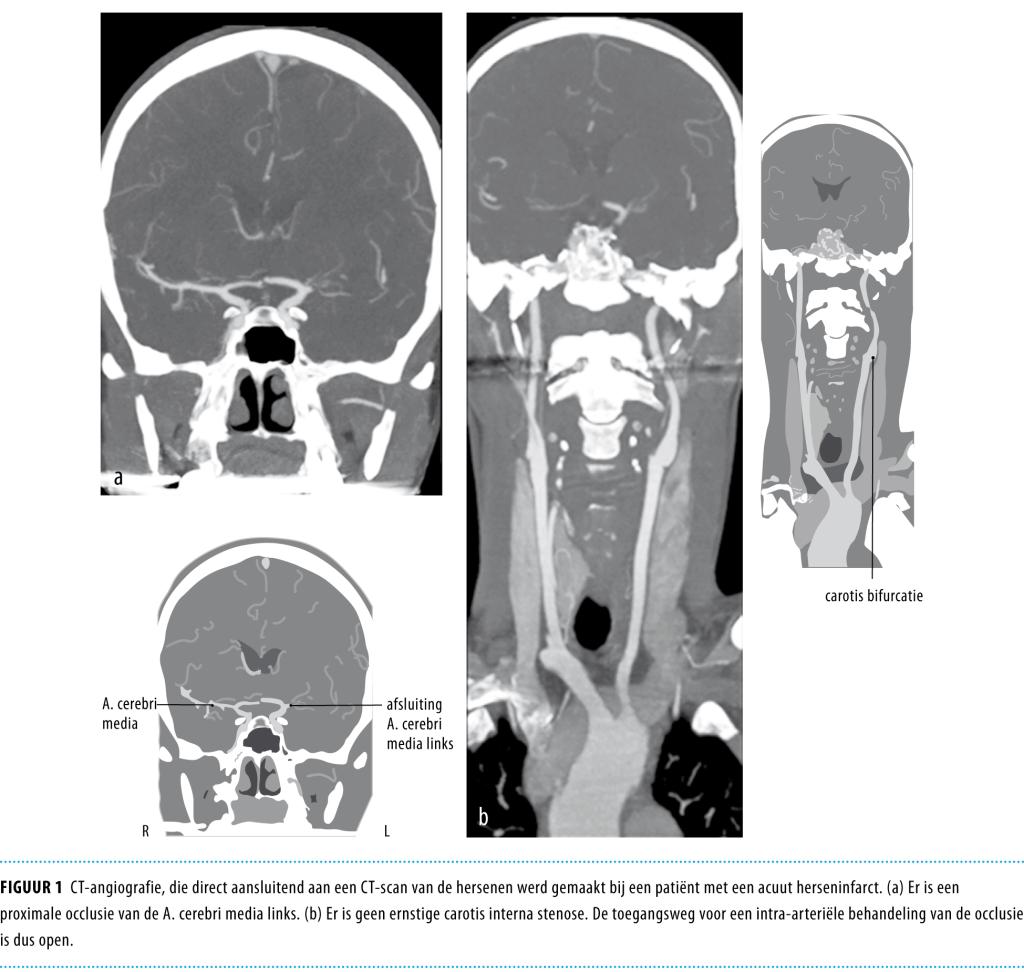

Figuur 1

Lokale trombolyse of IAT is een behandeling waarbij men via een punctie in de liesslagader een katheter opvoert tot aan de afsluitende intracraniële trombus, waarna vervolgens het trombolyticum ter plaatse wordt toegediend. Voorwaarde voor deze behandeling is dat er een trombus in een proximale cerebrale arterie aanwezig is die via een endovasculaire route bereikt kan worden (figuur 1).